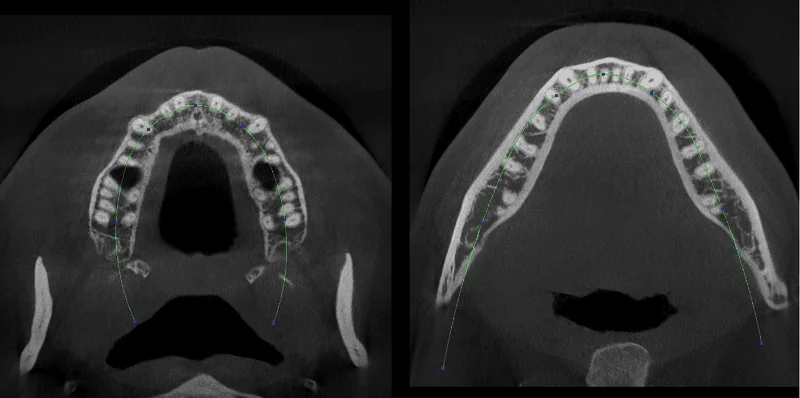

AI’s algorithm provides coordinates of the maxillary & mandibular arch, enabling an accurate outline of the arch anatomy.Patient Management Made Easy The purchasers will obtain their annual or bi-annual reminder for a dental checkup from AI-enabled software program. The diagnoses, prescriptions and former interactions inside healthcare organizations are available for dentists. Based mostly on this, a customized therapy plan may be offered. Drawing inspiration from IBM’s Watson platform, Dr John Kois of US had developed Evidentiae, cloud-based software for Dental Care. Other than giving an overall perspective, it gives ideas to improve the aesthetics and functionality of the patient’s dental structure. The Future Already there!